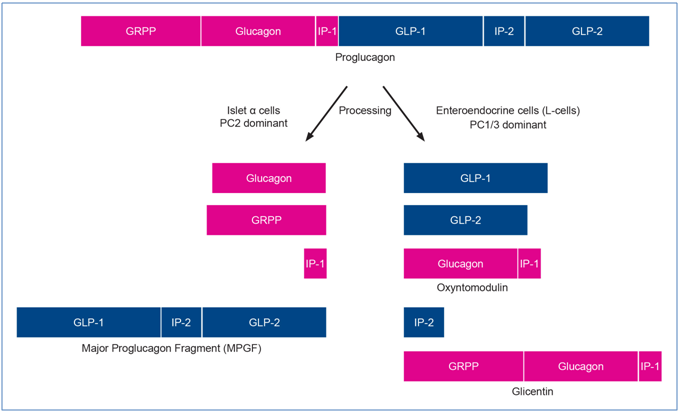

Glucagon is a 29 amino acid peptide structurally related to the secretin family of peptide hormones. Its sequence, synthesized as proglucagon, is highly conserved across mammalian species and is proteolytically processed into glucagon by prohormone convertase 2 (PC2) within the α cells of the pancreatic islets. Proglucagon is also expressed in the intestinal tract. In the intestinal enteroendocrine cells (L-cells), prohormone convertase 1/3 (PC1/3) is greater than PC2 action so the proglucagon sequence is cleaved to yield GLP-1, GLP-2, oxyntomodulin, glicentin and IP2 (Figure 2). There is evidence that PC1/3 is also expressed in the α cells of the pancreatic islets but at lower levels than PC2 suggesting that there is some pancreatic islet production of GLP-12.